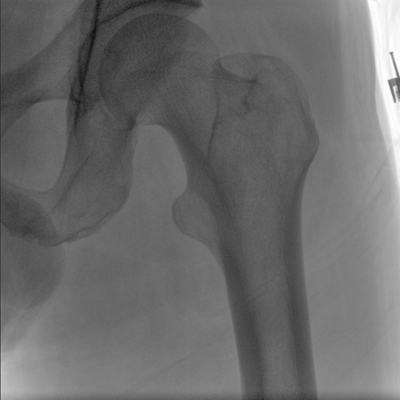

臨床適用科室:骨科、普通外科、矯形外科、創(chuàng)傷外科、泌尿外科、脊柱外科、疼痛外科、消化科、婦科等科室。

大尺寸動態(tài)平板探測器,高DQE、低噪聲、圖像清晰。采用多分辨率圖像增強處理技術(shù),不同部位不同圖像處理算法,滿足客戶多樣化的需求。